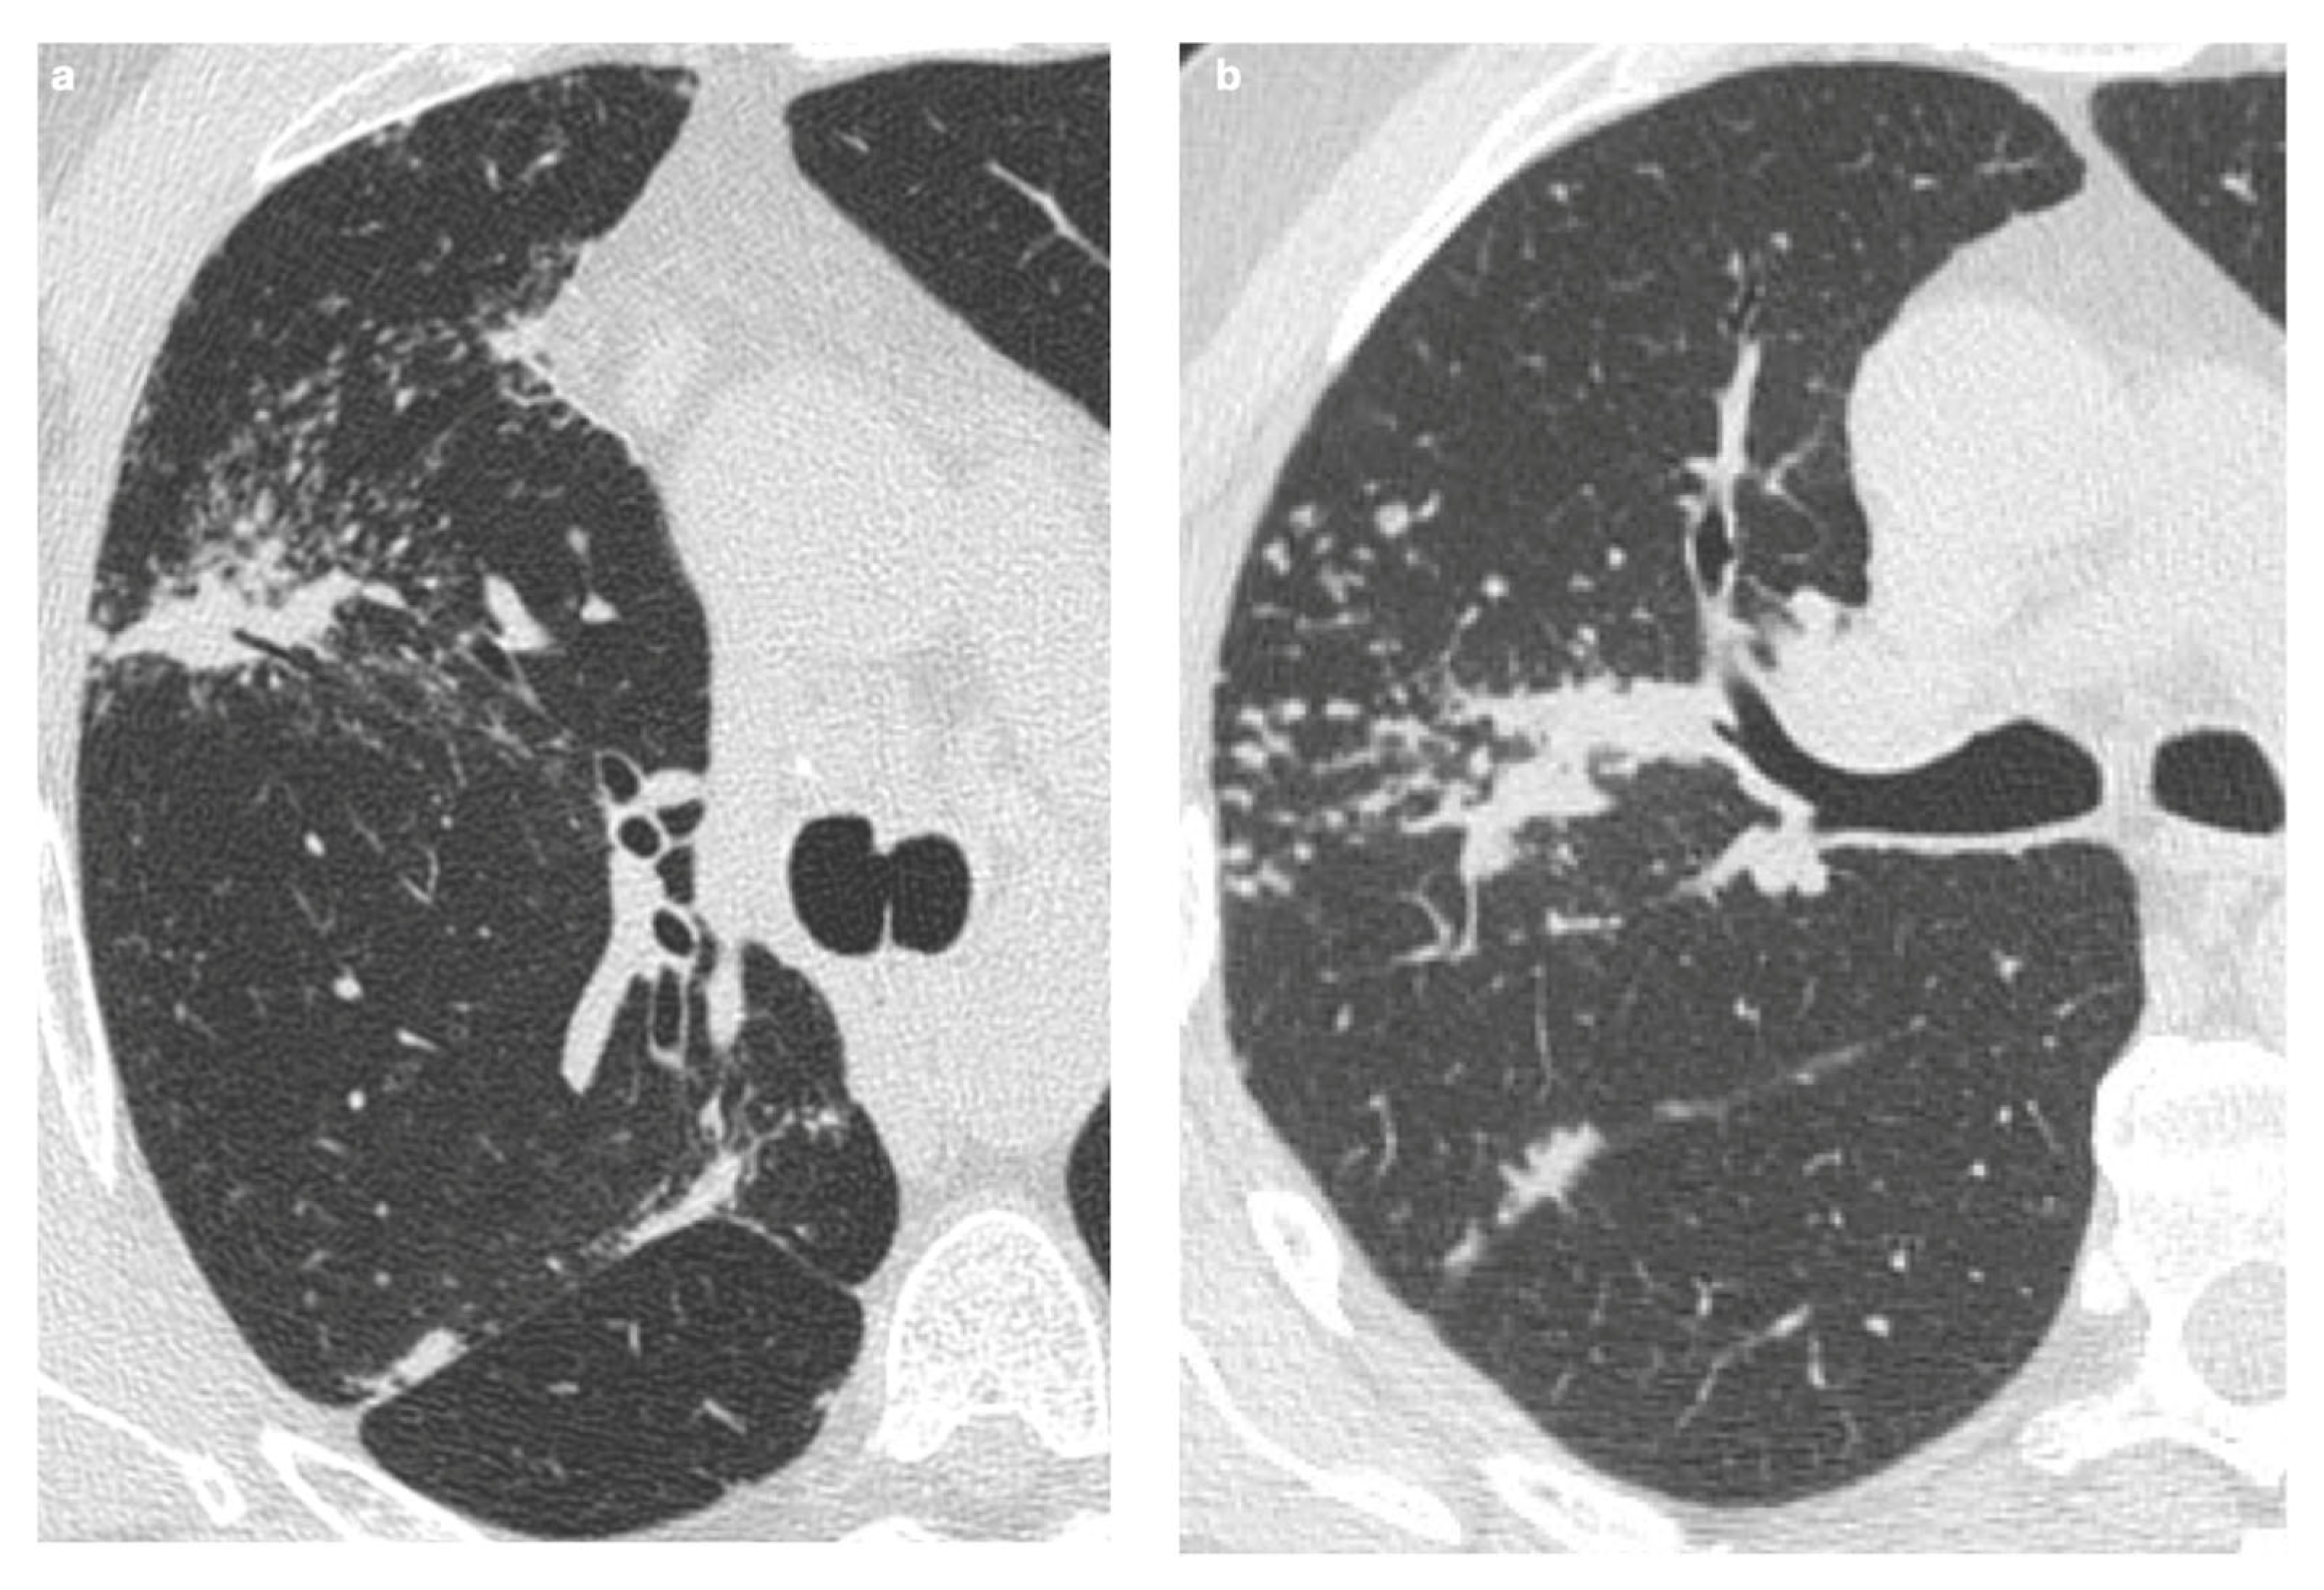

4.2.1. Nodules and Masses

4.2.2. Patchy Parenchymal Consolidation

4.2.3. Ground-Glass Opacities